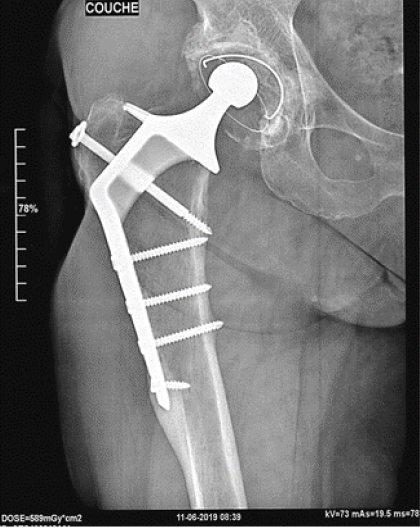

Eccentricity of the right metallic femoral head 0.7 cm loosening of polyethylene in 30 Years No calcar resorption, no screws fracture, periosteum inamovible apposition. Harris score: 100 (Figures 2-14).

Figure 11. Thirty years after surgery

Figure 12. Twenty-six years after surgery